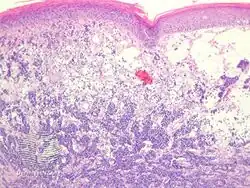

Diagnosis of MCC begins with a clinical examination of the skin and lymph nodes.[25] Following clinical exam, definitive diagnosis of Merkel cell carcinoma (MCC) requires examination of biopsy tissue to identify its histopathologic features.[3][25] An ideal biopsy specimen is either a punch biopsy or a full-thickness incisional biopsy of the skin including full-thickness dermis and subcutaneous fat. On light microscopy, MCC shows basaloid tumor nests with neuroendocrine features ("salt and pepper" chromatin, scarce cytoplasm, and brisk mitotic activity).[3][25] In addition to standard examination under light microscopy, immunohistochemistry (IHC) is also generally required to differentiate MCC from other morphologically similar tumors such as small cell lung cancer, the small cell variant of melanoma, various cutaneous leukemic/lymphoid neoplasms, and Ewing's sarcoma. Neuroendocrine molecular markers such as synaptophysin or chromogranin A are characteristic of MCC and other neuroendocrine tumors, while other markers such as PAX5 or cytokeratin 20 can distinguish MCC from these tumors.ref name=Kervarrec2019/>[4] Longitudinal imaging may also help in ruling out a diagnosis of metastatic small cell lung cancer. Once an MCC diagnosis is made, a sentinel lymph node biopsy as well as other imaging is recommended as a part of the staging work-up needed to determine prognosis and subsequent treatment options.[3][25]

Merkel-cell carcinoma/pathology -

Micrograph of a Merkel-cell carcinoma. H&E stain -